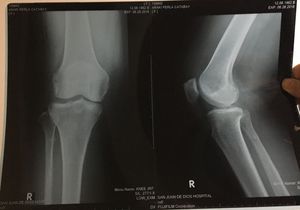

A 56 years old woman has exclusive pain on the right of her knee. Is this a normal x-ray? If not what is the findings?

OA

osteoarthritis of knee joint

Osteoarthritis